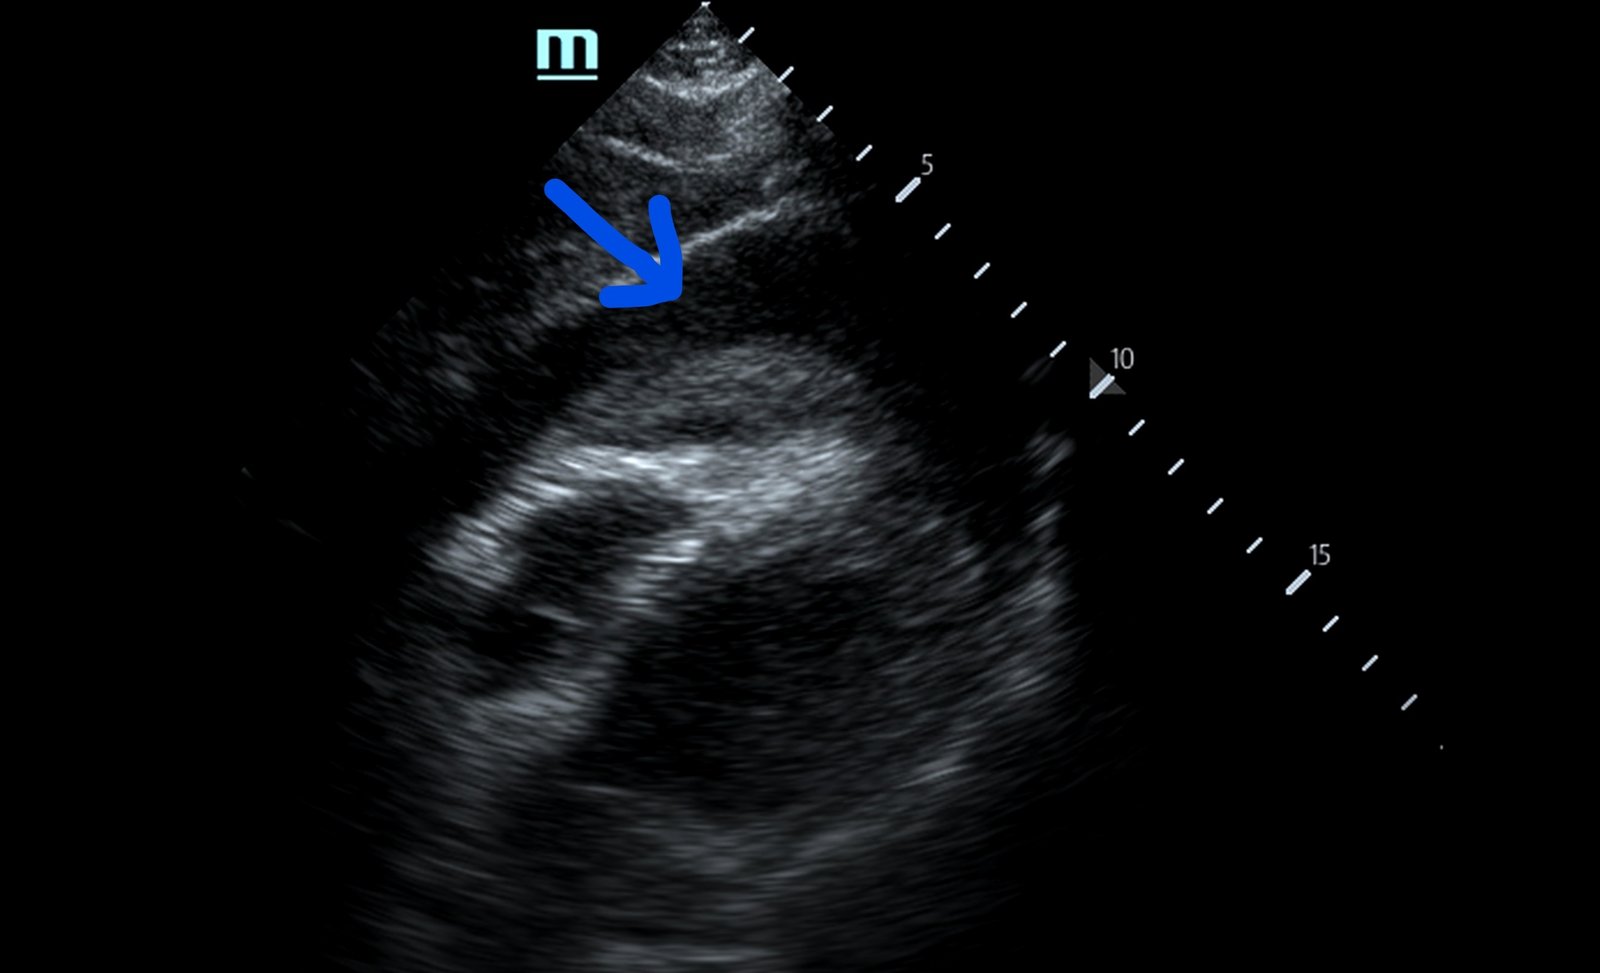

Focused assessment with sonography in trauma (FAST) scan was positive for a clinically significant pericardial effusion as evidenced by the hypoechoic fluid around the myocardium, indicated by the blue arrow in image 2. Findings are also consistent with tamponade process as evidenced by restricted expansion and collapse of the right ventricle during diastole. The hyperechoic floating structure between the pericardium and myocardium, adjacent to the right ventricle, represents a pericardial clot, indicated by the white arrow.The density of the pericardial clot differs from that of the myocardium, thus serving as an additional variable to avoid confusing this as part of the myocardial structure.

In our patient, the use of point-of-care ultrasound was able to quickly make the diagnosis of cardiac tamponade and clotted blood in the pericardium. Knowing this information allowed this patient to undergo definitive management. In this case, the patient had large bore peripheral intravenous access established and was taken emergently to the operating room for a thoracotomy. This revealed a left ventricle stab wound, inferior vena cava through-and-through stab wound, pericardial effusion with tamponade and clotted blood. A pericardiectomy was performed and the patient eventually stabilized.